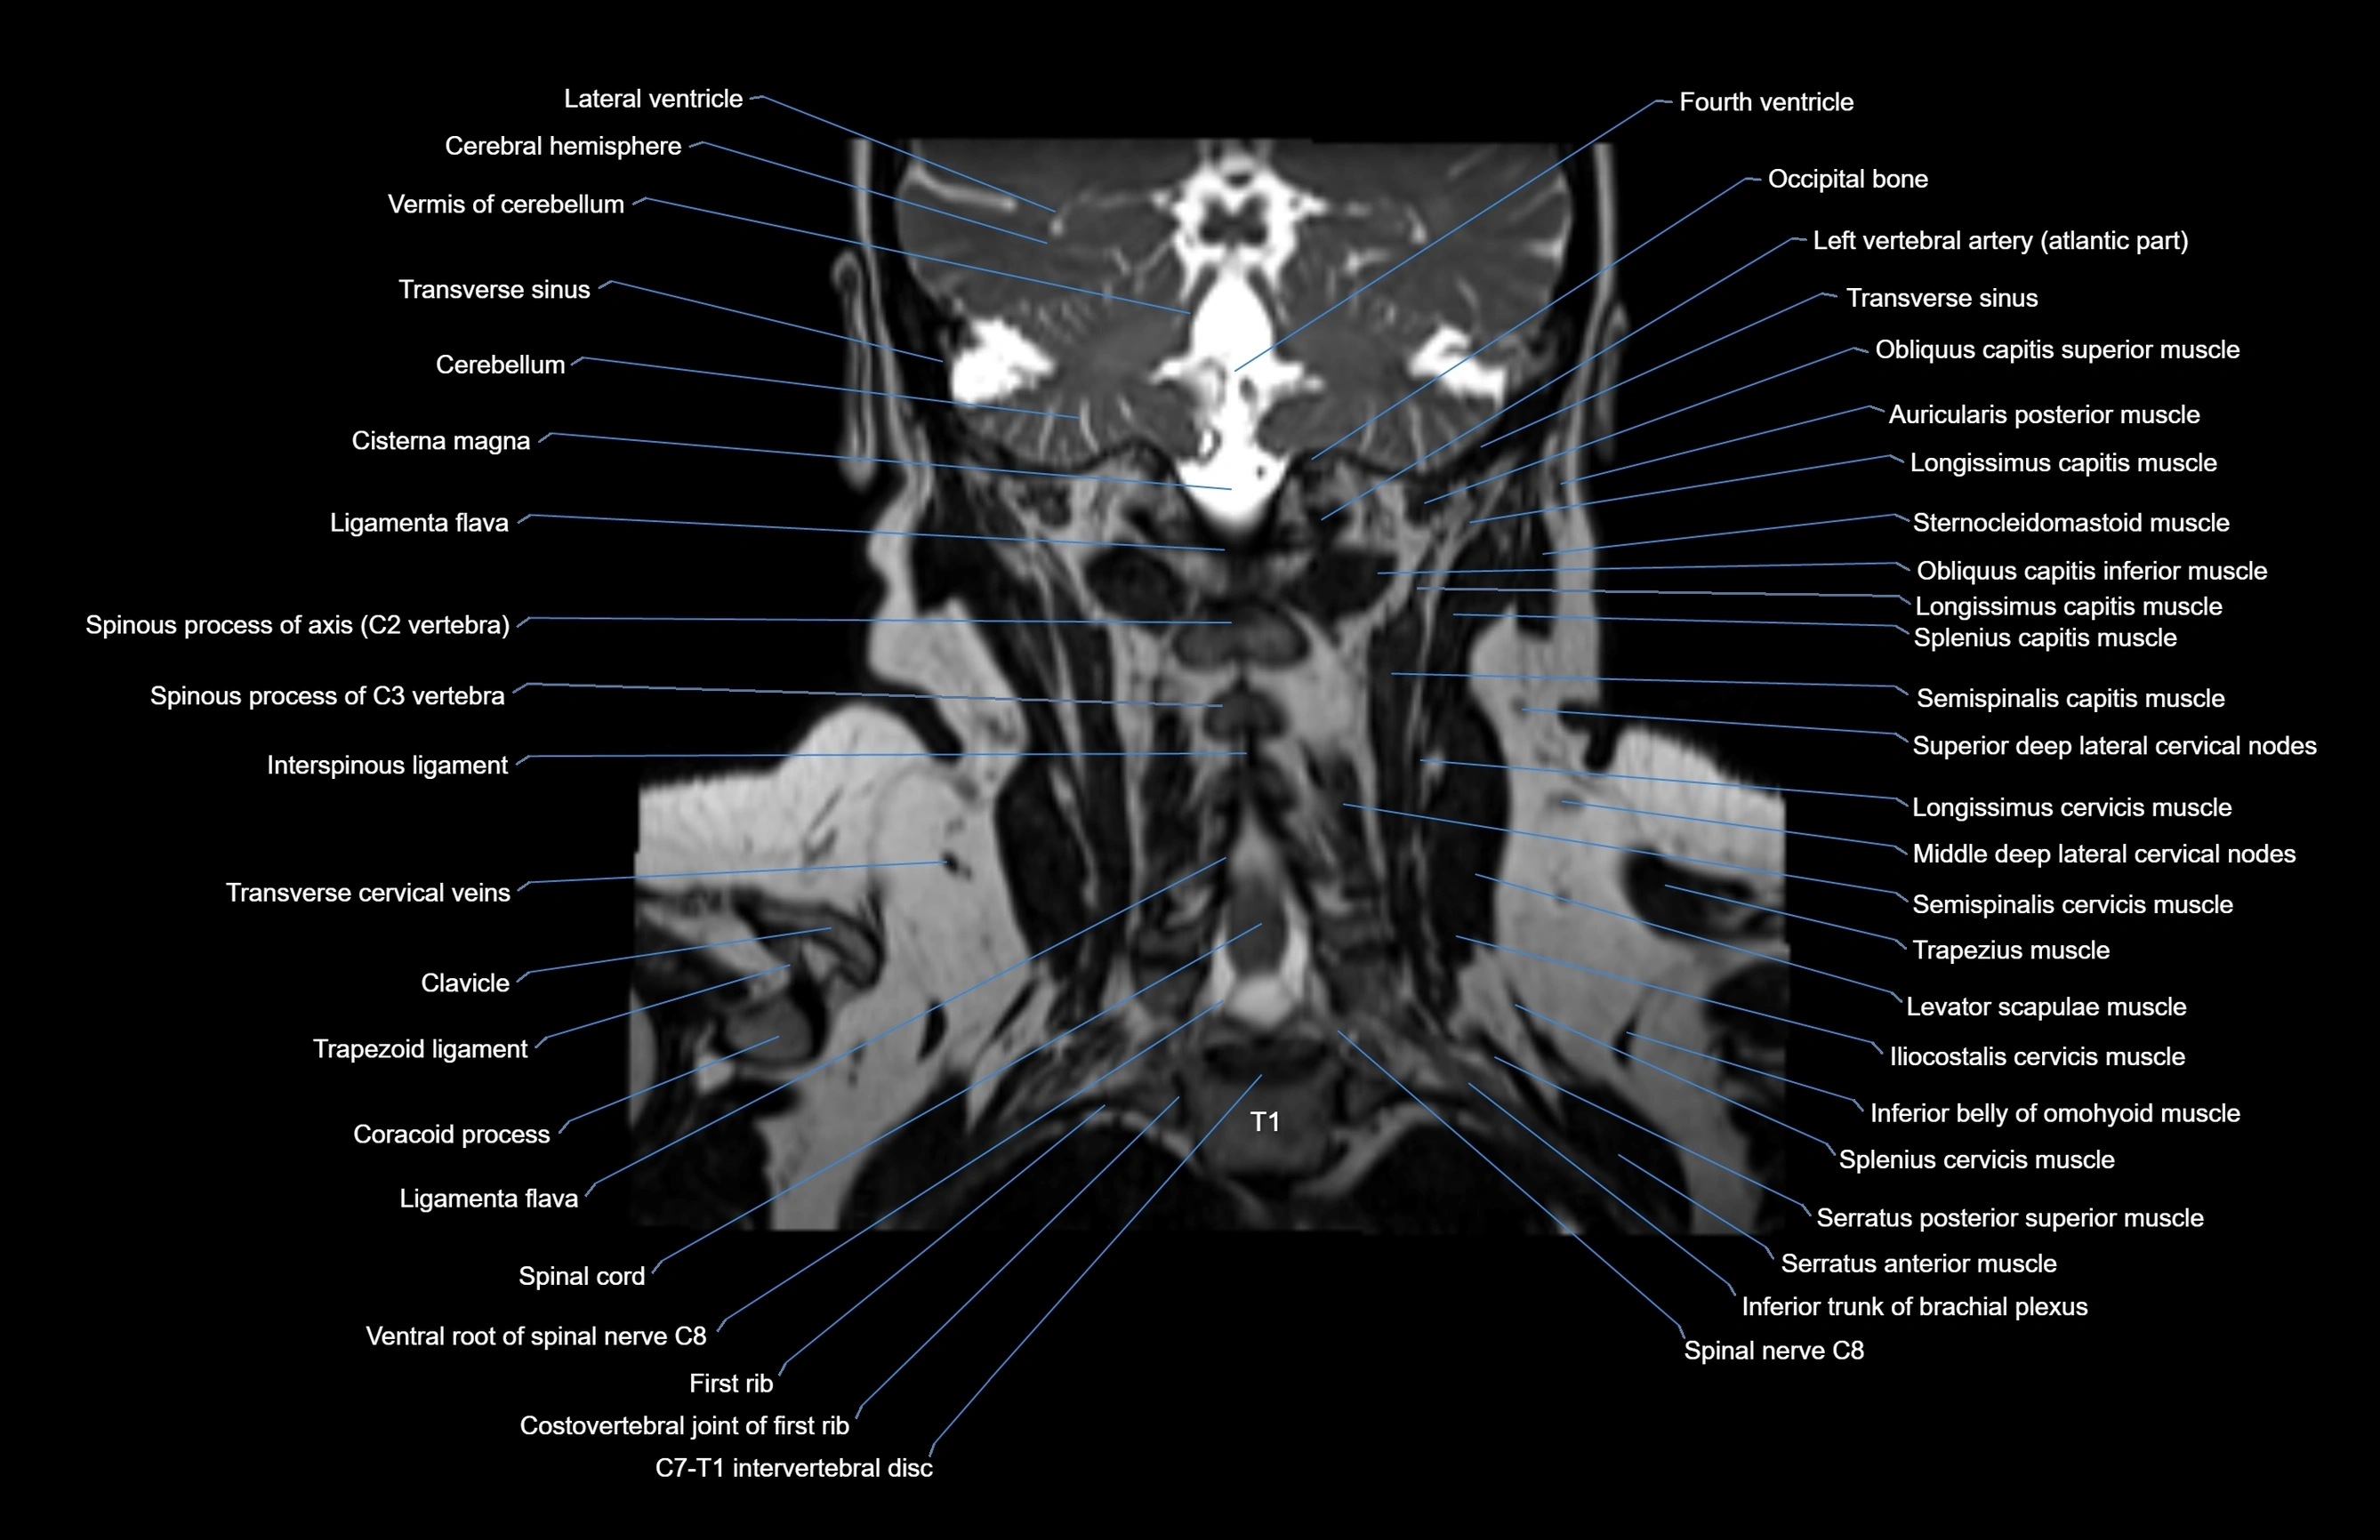

- Cerebellum

- Cisterna magna

- Interspinous ligament

- Left vertebral artery (atlantic part)

- Ligamenta flava (Ligamentum flavum)

- Occipital bone

- Levator scapulae muscle

- Longissimus cervicis muscle

- Semispinalis capitis muscle

- Semispinalis cervicis muscle

- Spinal cord

- Splenius cervicis muscle

- Trapezius muscle

- First rib

- Multifidus muscles